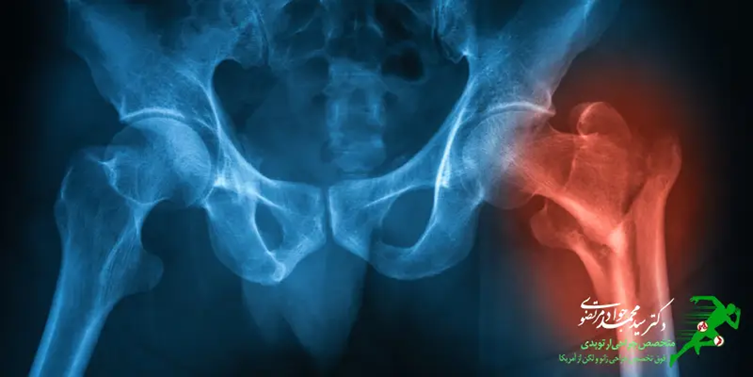

تشخیص شکستگی لگن

ابتدایی ترین روش تشخیص بیماری گرفتن شرح حال از وضعیت بیمار و اطلاع از سوابق پزشکی است. در این صورت متخصص ارتوپدی از علائم بیمار همچون شکاف، تورم، کبودی و یا تغییر شکل مطلع می شود و به منظور تشخیص صحیح و دقیق تر انجام آزمایش های خاصی را برای تایید ارزیابی اولیه تجویز می نماید.

انجام آزمایش های تصویربرداری همچون MRL و سی تی اسکن به منظور تشخیص دقیق تر لازم و ضروری خواهد بود. ام.آر.آی به نسبت اشعه ایکس دقیق تر بود و شکستگی استخوان ران را به صورت کاملا واضح نشان خواهد داد، در صورتی که در روش تصویربرداری سی تی اسکن تصاویری از استخوان لگن، عضلات، بافت ها و چربی های اطراف ناحیه مورد نظر کاملا مشخص خواهد شد.